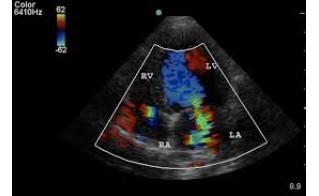

Diagnostiek en Beeldvorming; Voor een nauwkeurige diagnose beschikken wij over de nieuwste technologieën op het gebied van beeldvorming:

- Digitale röntgen en Echo: Inclusief geavanceerde hartecho's met kleuren-doppler.